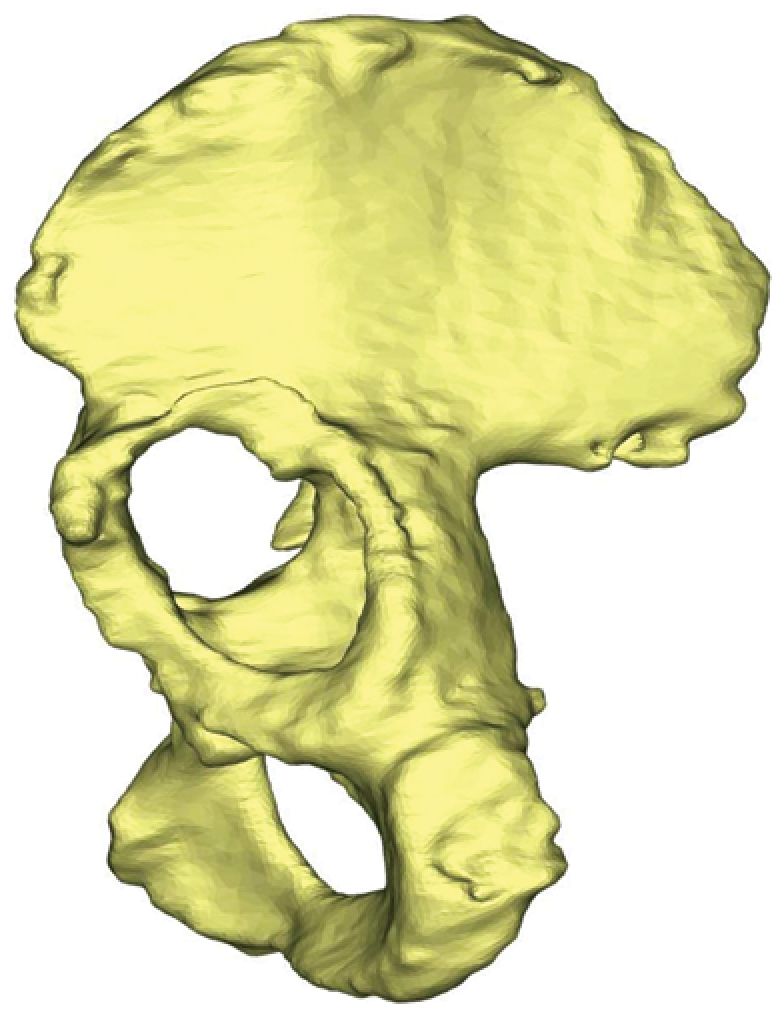

X-rays of patients with defects | ||||

Three-dimensional reconstructions of the pelvis of the same patients from the side of defect | ||||

Lytic defects and complete defects of the anterior column, despite their extent, require the restoration of the sphericity of the acetabular region, which can be reconstructed using bone grafts, augments, and standard hemispherical components (Figure 2 a, b).

Figure 2. Various options for acetabular reconstruction in Paprosky type 3B defect: a — lytic acetabular defect reconstructed using impaction bone grafting with implantation of a standard cemented acetabular component; b — complete anterior column defect reconstructed with an augment and a hemispherical acetabular component; c — complete medial wall defect reconstructed with augmentation and combined implantation of a hemicap cage; d — combination of complete medial wall and anterior column defects reconstructed with a Burch-Schneider antiprotrusio cage and a cemented acetabular component; e — combination of complete medial wall and posterior column defects reconstructed with a patient-specific acetabular component